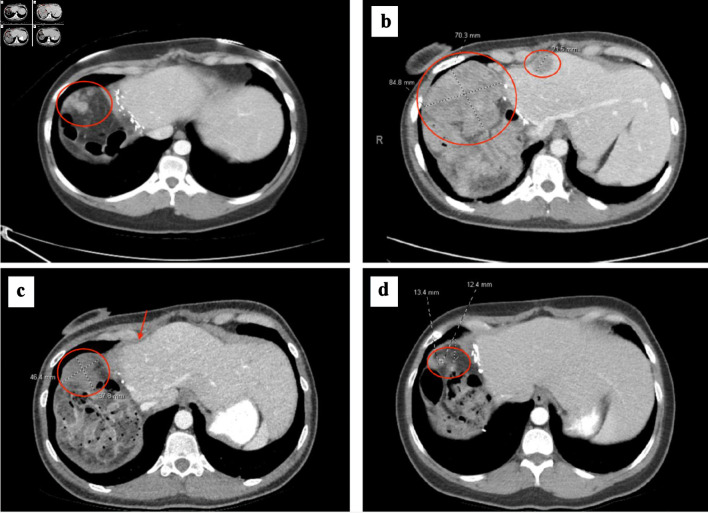

肝细胞癌(HCC)通常在晚期才被确诊,尽管采取了治疗性干预措施,但仍经常复发,导致生存率低下。前线系统疗法包括联合免疫疗法和酪氨酸激酶抑制剂。我们报告了一例患有慢性乙型肝炎和丙型肝炎合并感染的非肝硬化 HCC 的 38 岁女性患者的病例。阿特珠单抗/贝伐单抗和来伐替尼均导致病情恶化,随后她接受了吉西他滨和奥沙利铂(GEMOX)化疗,几个月后,影像学检查显示其临床反应良好,甲胎蛋白(AFP)恢复正常。经过广泛的多学科讨论,她接受了囊肿切除手术(CRS)和腹腔热化疗(HIPEC),切除了所有可见的大肿瘤。病理结果显示她的病理反应完全。她在术后又接受了两个月的化疗,并在治疗结束后继续接受密切监测。据我们所知,这是首例在标准免疫疗法和酪氨酸激酶抑制剂治疗进展后,通过CRS/HIPEC治疗腹膜转移的HCC患者对GEMOX化疗产生完全病理反应的病例。在本报告中,我们回顾了目前 HCC 的全身治疗情况。我们强调了在目前的临床实践中较少使用的细胞毒性化疗在选定的 HCC 患者中的潜在考虑,并讨论了 CRS/HIPEC 在腹膜转移治疗中的作用。我们亟需对全身治疗反应的预测因素进行进一步研究。多学科治疗可最终延长晚期 HCC 患者的生存期。

Hepatocellular carcinoma (HCC) is often diagnosed at a late stage and frequently recurs despite curative intervention, leading to poor survival outcomes. Frontline systemic therapies include combination immunotherapy regimens and tyrosine kinase inhibitors. We report a case of a 38-year-old woman with chronic hepatitis B and C coinfection-associated non-cirrhotic HCC, which recurred in the peritoneum after initial resection of her primary tumor. Disease progression occurred on both atezolizumab/bevacizumab and lenvatinib, and she was subsequently treated with gemcitabine and oxaliplatin (GEMOX) chemotherapy and exhibited a profound clinical response on imaging with normalization of alpha fetoprotein (AFP) after several months. Following extensive multidisciplinary discussion, she underwent cytoreductive surgery (CRS) with hyperthermic intraperitoneal chemotherapy (HIPEC) that removed all visible macroscopic tumor. Her pathology demonstrated a complete pathologic response. She received two additional months of postoperative chemotherapy, and then proceeded with close monitoring off therapy. To our knowledge, this is the first reported case of a complete pathologic response to GEMOX chemotherapy in the context of CRS/HIPEC for peritoneal metastases in HCC, after progression on standard immunotherapy and tyrosine kinase inhibitor treatments. In this report, we review the current systemic treatment landscape in HCC. We highlight potential consideration of cytotoxic chemotherapy, which is less frequently utilized in current practice, in selected patients with HCC, and discuss the role of CRS/HIPEC in the management of peritoneal metastases. Further investigation regarding predictors of response to systemic treatments is strongly needed. Multidisciplinary management may ultimately prolong survival in patients with advanced HCC.